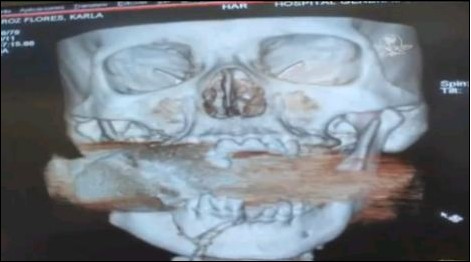

X光掃描圖顯示,一枚手榴彈卡在了弗洛雷斯的上下頜骨之間。

當弗洛雷斯醒來時,她已被送到了醫院。醫生們一開始還以為弗洛雷斯的臉部受到了石塊的重擊,但在進行X光掃描后發現,在她的上下頜骨之間卡著一枚未爆炸的手榴彈。有關專家判斷,該手榴彈是經過發射器投擲的,一旦被引爆將會危及周圍十米以內的人員。